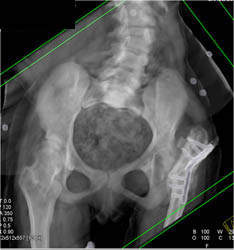

Diagnosis

Cellulitis